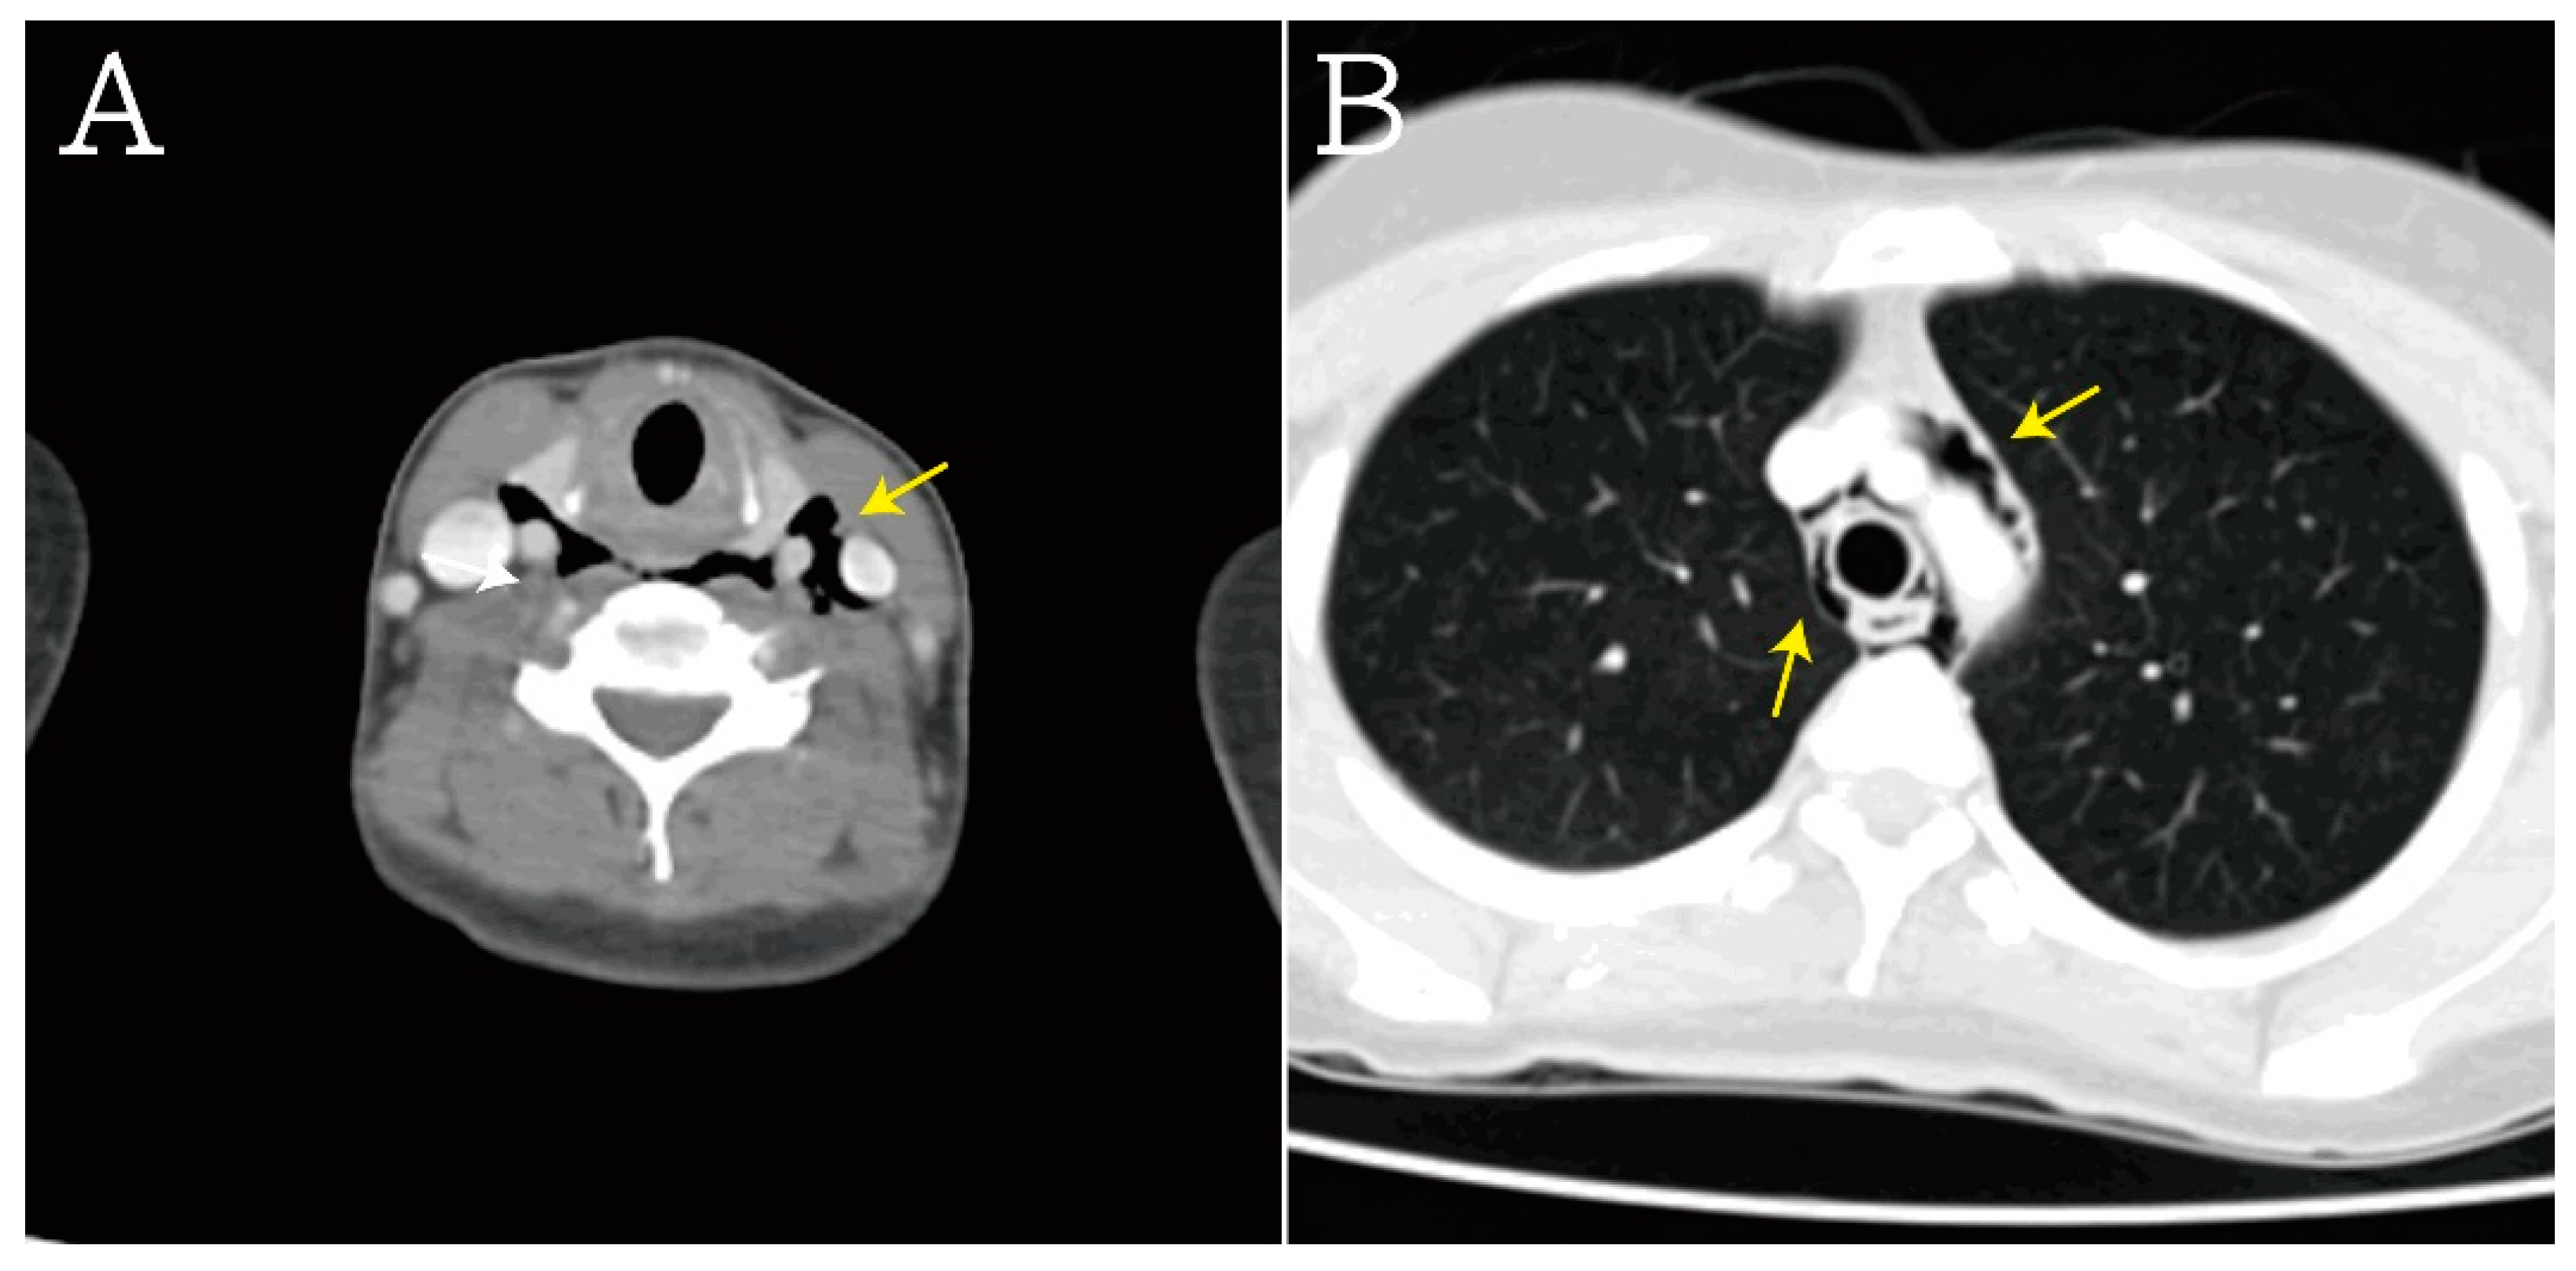

Figure 3.

In computed tomography scans, these results were also noted, including (A) subcutaneous emphysema (yellow arrow), (B) pneumomediastinum, periaortic gas, and pericardiac gas (yellow arrow).